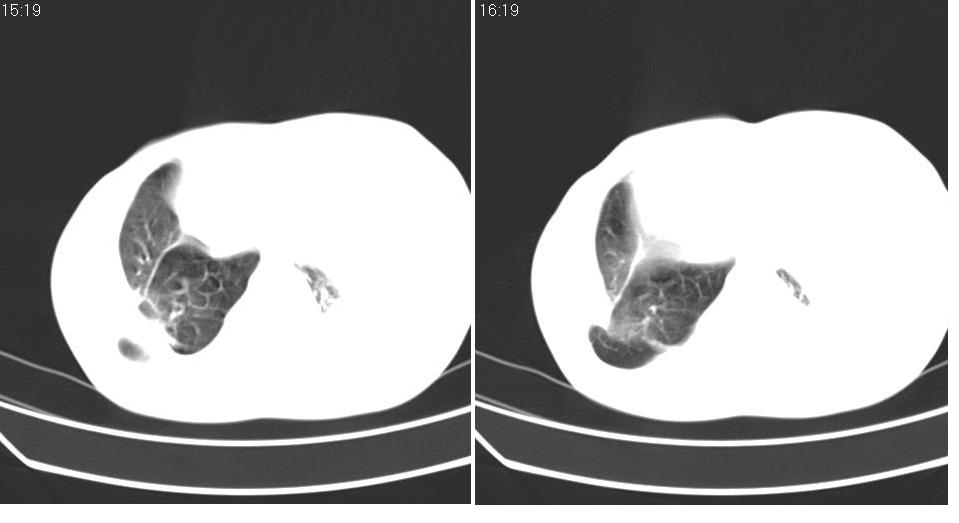

以下是引用苯小孩在2007-6-27 15:09:00的发言:[br]考虑:1、右肺继发性肺结核.2、双侧包裹性积液<胸腔及叶间>3、双侧局部胸膜增厚.[br]建议胸水化验检查.

以下是引用yanghaochen88在2007-6-27 15:08:00的发言:[br]双肺上野散在粟粒状影、包裹性积液、胸膜增厚粘连、叶间积液---tb,至于分型还得结合病史体征细究妥当些。